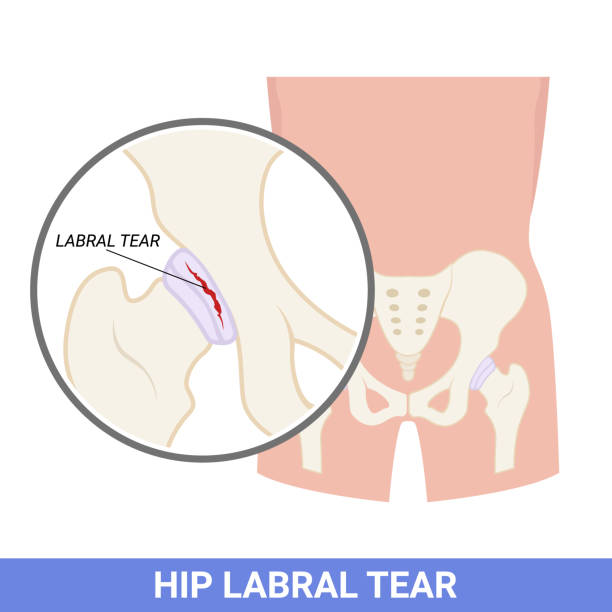

- Hip Labral Tear:

- It is a tear in the ring of cartilage (labrum) that follows the outside rim of the hip socket.

- Common symptoms are deep groin pain, clicking or locking of the hip, stiffness.

- Common causes are trauma, repetitive movements (like sports), or structural abnormalities.

- If not treated it can lead to arthritis.